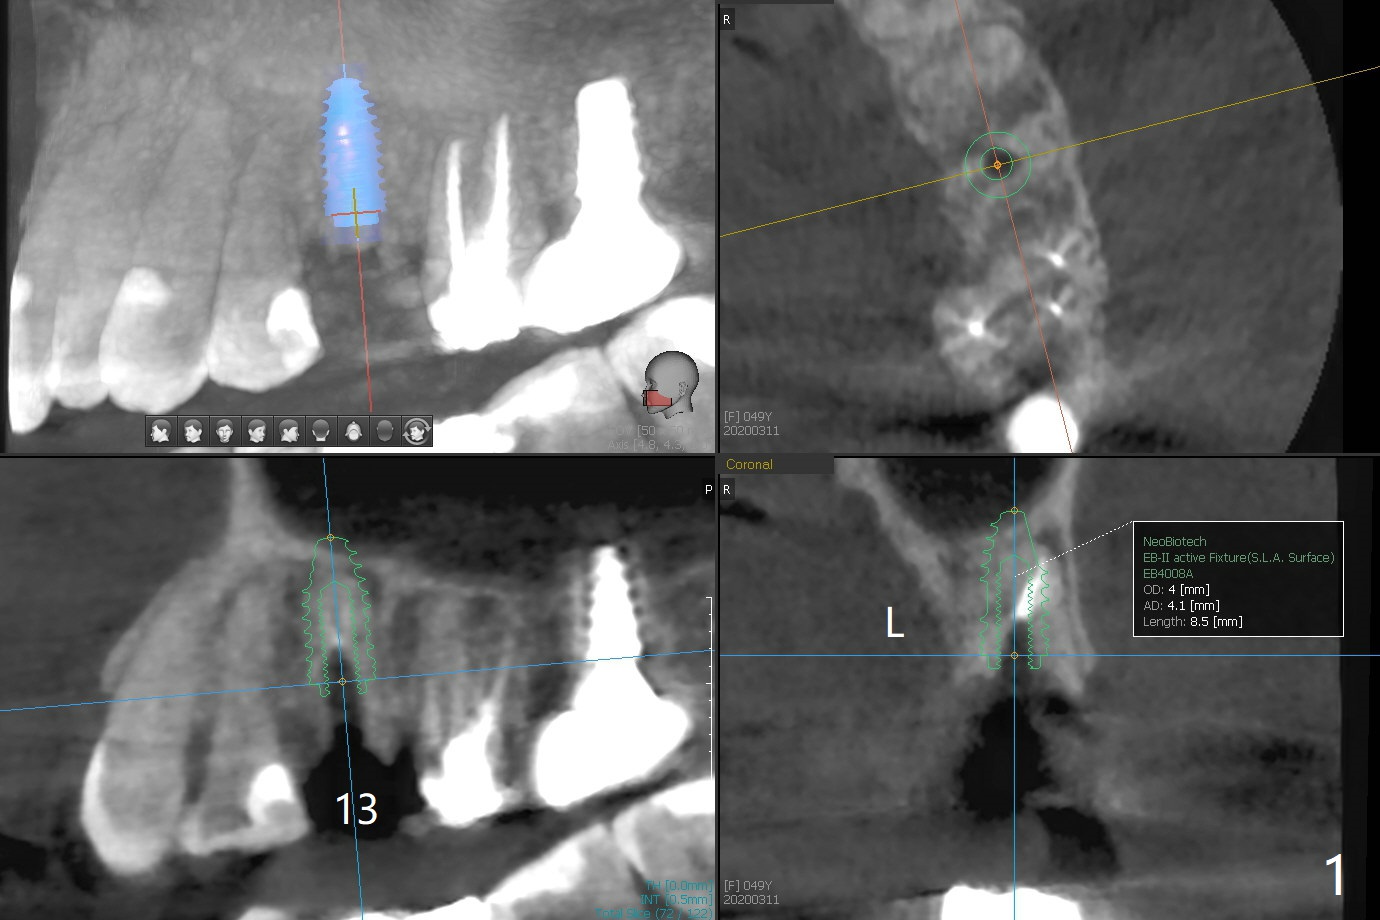

A 49-year-old woman has loose splinted crowns between #13 and 14. After removal of the crowns, the tooth #13 is found non-salvageable (Fig.1). A 4 or 4.5 x 8.5 or 10 mm implant should be able to achieve primary stability because of engagement of the implant into the mesial and distal walls of the socket and the sinus floor. Splinted provisional should provide with additional retention. There is no much need for socket shield, since there is no mesial or distal crestal bone loss (associated with food impaction). If the crown is short, there is no concern about buccal gingival recession. In fact the mesial papilla is more apical than the distal one (Fig.2 *), corresponding to the more apical crest (Fig.3 *). To prevent further mesial crestal loss post extraction, socket shield seems necessary. There appears that the implant is placed distal enough so that a small portion of the mesial root (Fig.4,5 R) is able to be saved. Fig.6 is the occlusal view of the residual root of the tooth #13. The mesial sheath will be kept (Fig.7,8, as compared to Fig.3).